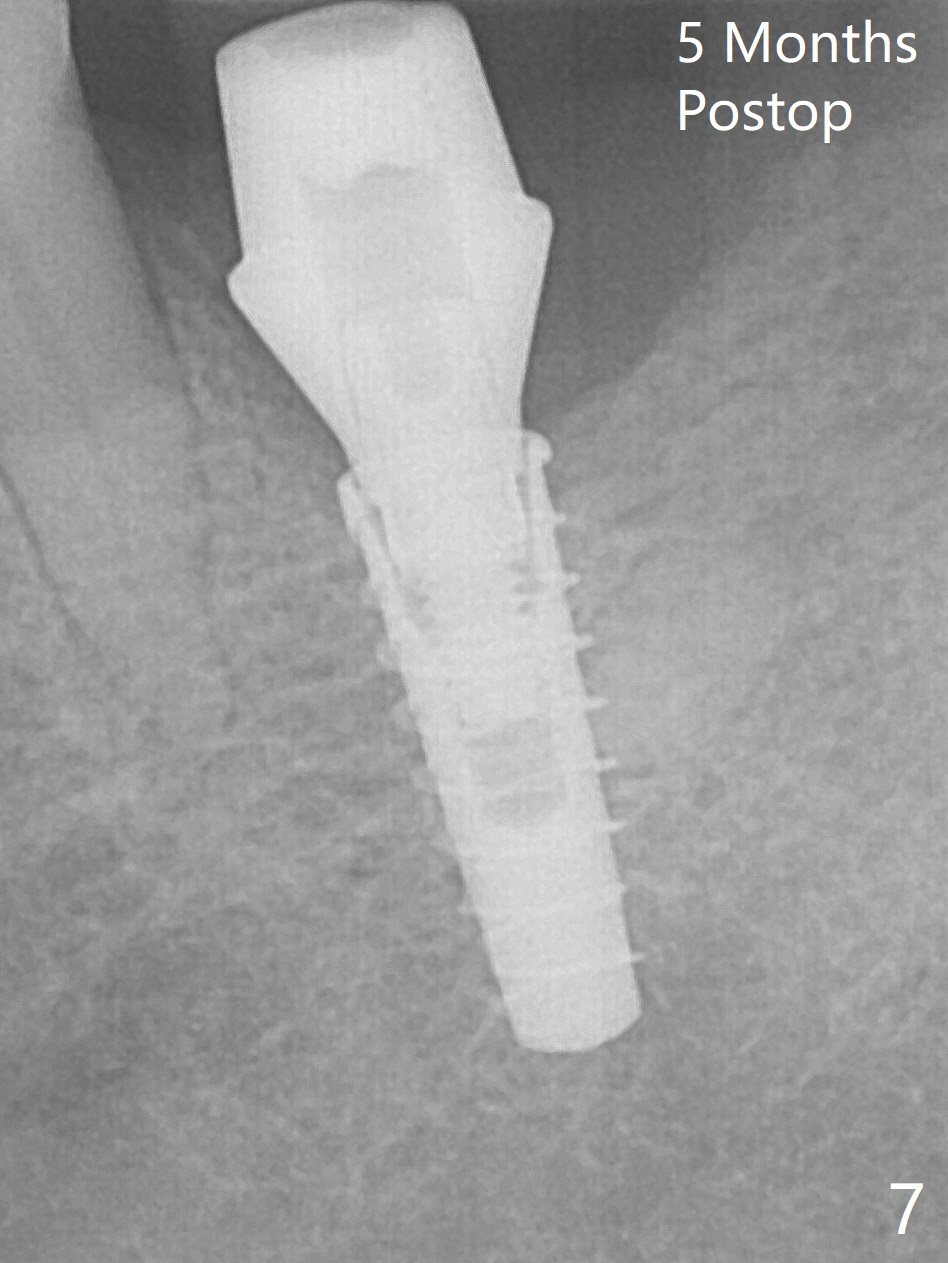

After incision over the narrow ridge at #30 (Fig.1) and ridge reduction (Fig.2 black area on the top; Fig.4 arrowheads), a 1.6 mm drill is used (Fig.2 (CBCT coronal section) long vertical black area) to start BEB (bone expansion and Bending). It is expected that the cortical and cancellous bone of the buccal (B) and lingual (L) plates can be expanded after use of Magic Expanders (ME) and 1.6 mm drill alternatively. In fact it appears that only the cancellous bone is pushed after MEs from 3 to 4.3 mm (Fig.3 arrows). There is no apparent cortical bone bending. There may be cancellous bone condensation. Dummy (Fig.4) and definitive (Fig.5) implants (4x11 mm) are placed. Since torque is 20 Ncm, a 5.5x4 mm healing abutment is placed (Fig.5,6 H). The opposing tooth is supraerupted; intrusion is pending. A 6x4(2) mm abutment is placed with a provisional 2 months postop. There is enough occlusal clearance. Impression is taken 5 months postop with difficulty because of subgingival margin (Fig.7). After cementation, the patient feels discomofort, which is relieved when the mesial embrasure is enlarged. Return to Lower Molar Immediate Implant, Armaments Xin Wei, DDS, PhD, MS 1st edition 12/14/2017, last revision 09/16/2018